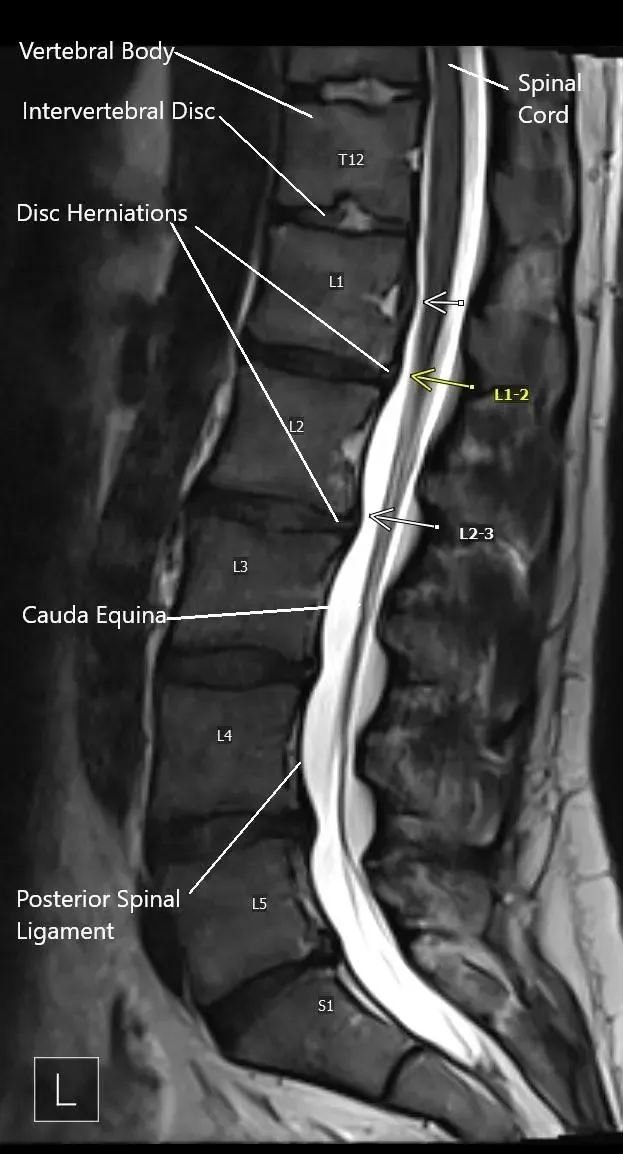

MRI image showing multiple disc herniations.

Imaging tests help confirm the diagnosis:

- X-rays: Rule out other causes of back pain.

- MRI: Shows disc herniation and nerve compression.

- CT scan or myelogram: Used if MRI is not possible.

- Electrodiagnostic studies (EMG/NCS): Assess nerve function if symptoms persist or are unclear.